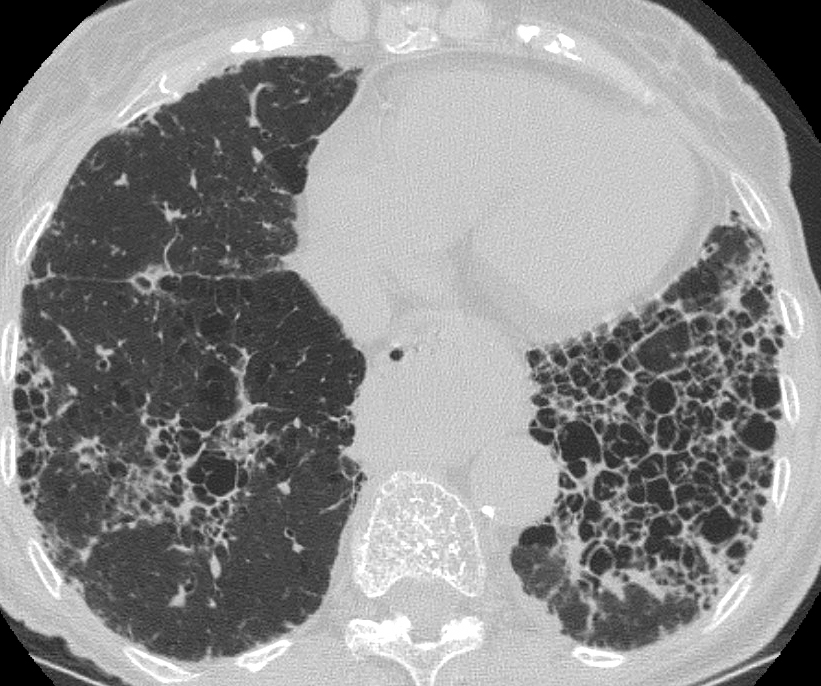

Gallery Pulmonary Fibrosis IPF Case 6c

Case 6c